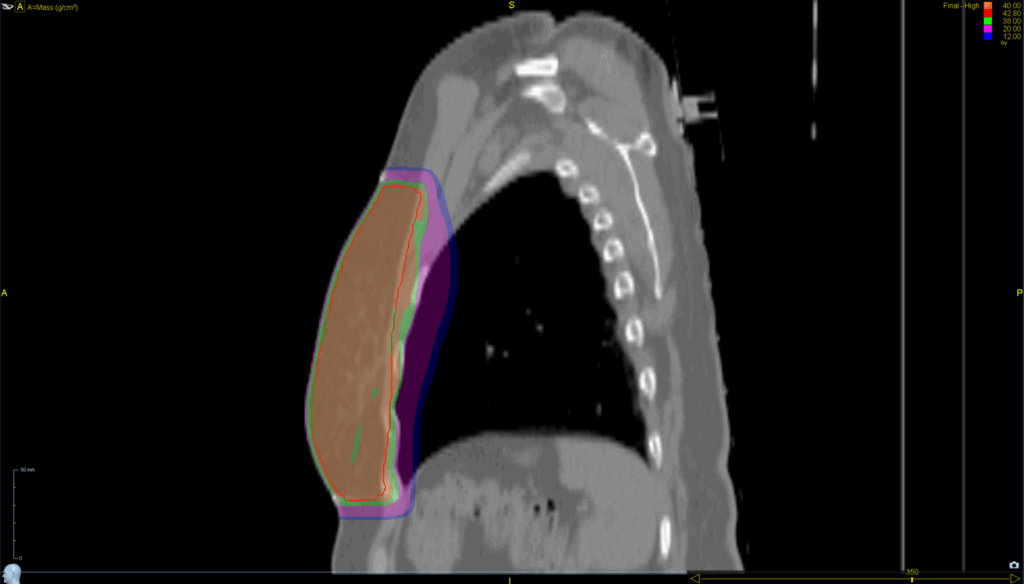

Left Whole Breast

Planning CT Images

Treatment Plan Images

Treatment Planning Highlights

PTV(s) Volume, Length

617 cc, 18 cm

Mode

- TomoDirect™

- 4 angles

- TomoEDGE™ 5 cm